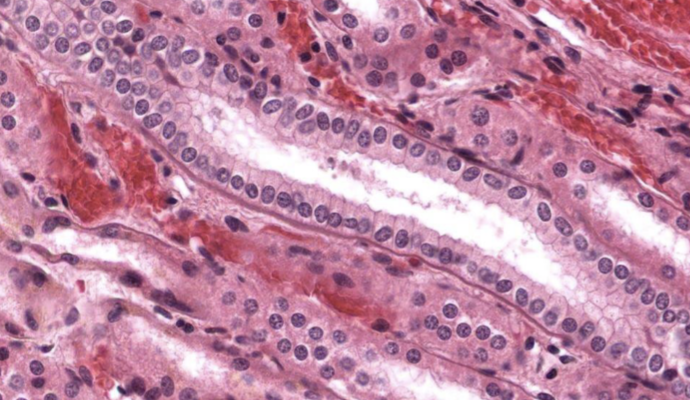

pseudoestratificado